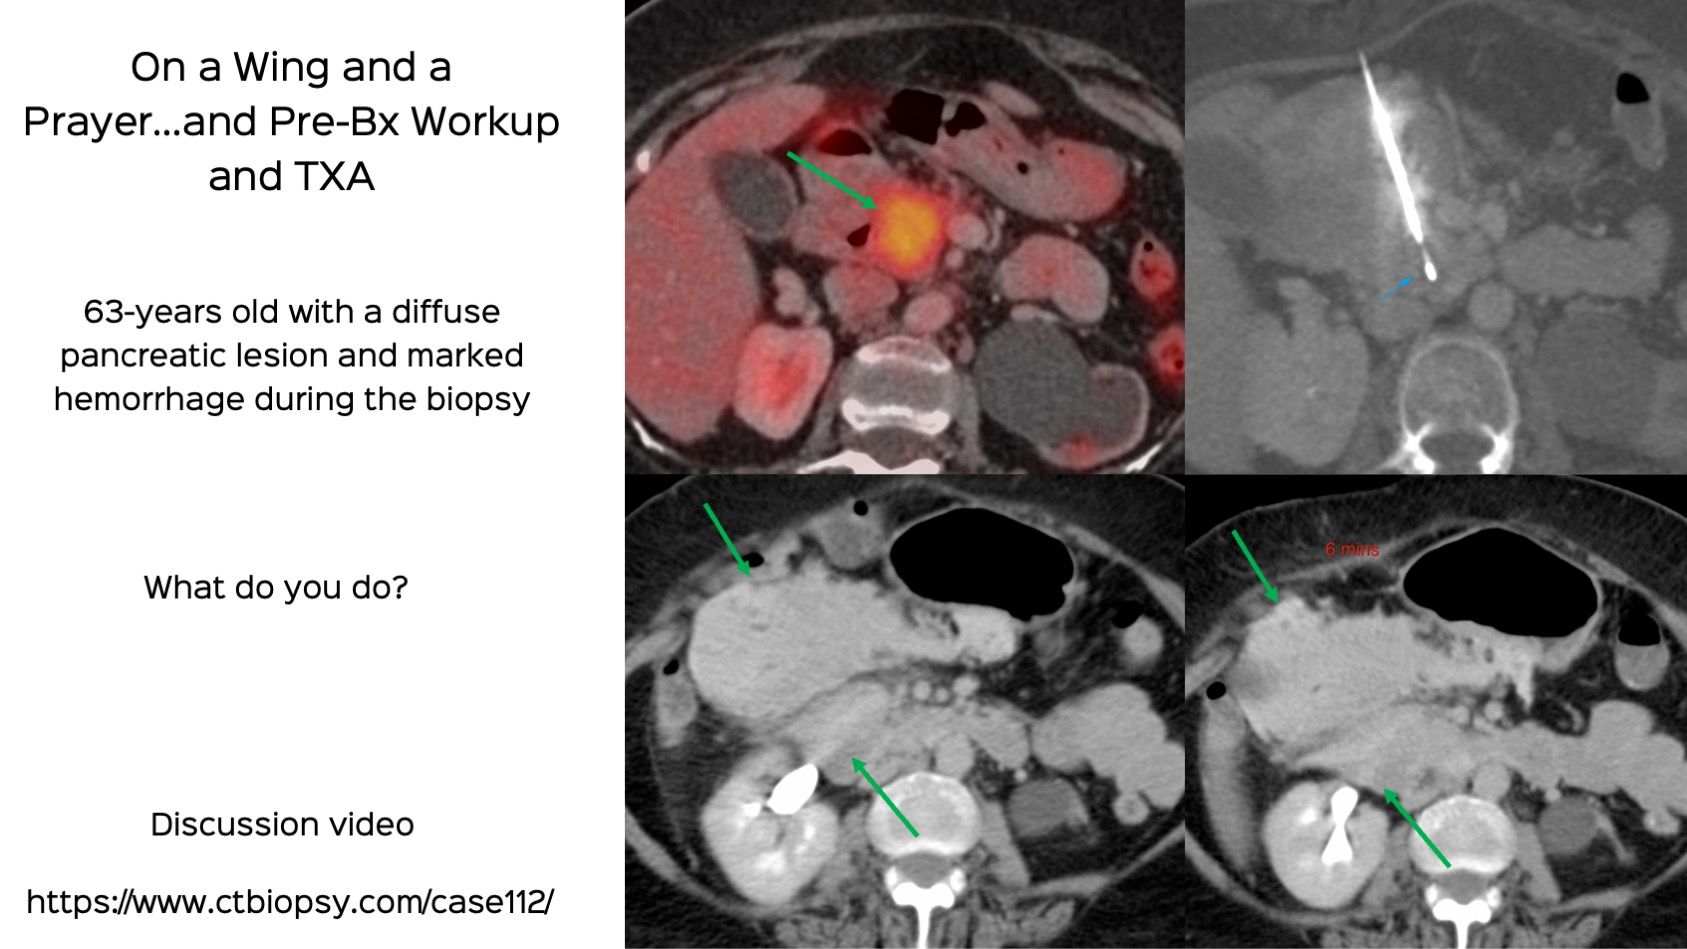

Case 112: Pancreatic Head Biopsy and Hemorrhage - On a Wing and a Prayer...And Pre-Bx Workup and TXA

Bhavin Jankharia - 20 December 2022